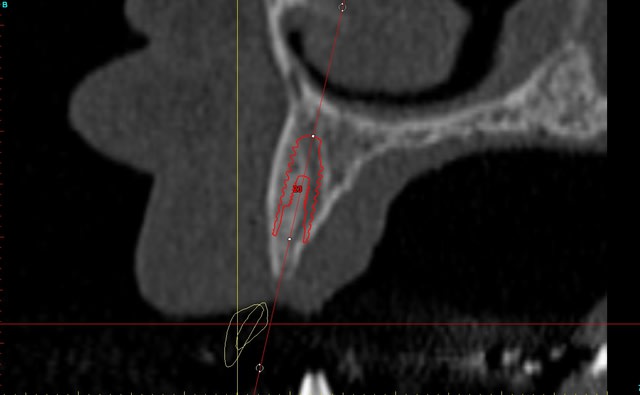

Dar axial lebnbu - Eugenol

Dar axiali qui1is - Eugenol

Dar11 cyo3el - Eugenol

Dar13 alznrp - Eugenol

Dar13i aujibg - Eugenol

Dar14 actm24 - Eugenol

Dar15 zvi82y - Eugenol

Dar23i g6nxds - Eugenol

Dar24 vzfroa - Eugenol

Dar25 lcptyk - Eugenol

Dar 3d xkb3uv - Eugenol

Dar  3di ngfcc4 - Eugenol

Dar  3dl fwmdk6 - Eugenol

Céramik

image 8, il semble y avoir une zone entre le greffon et l'os ?

C'est intégré ?